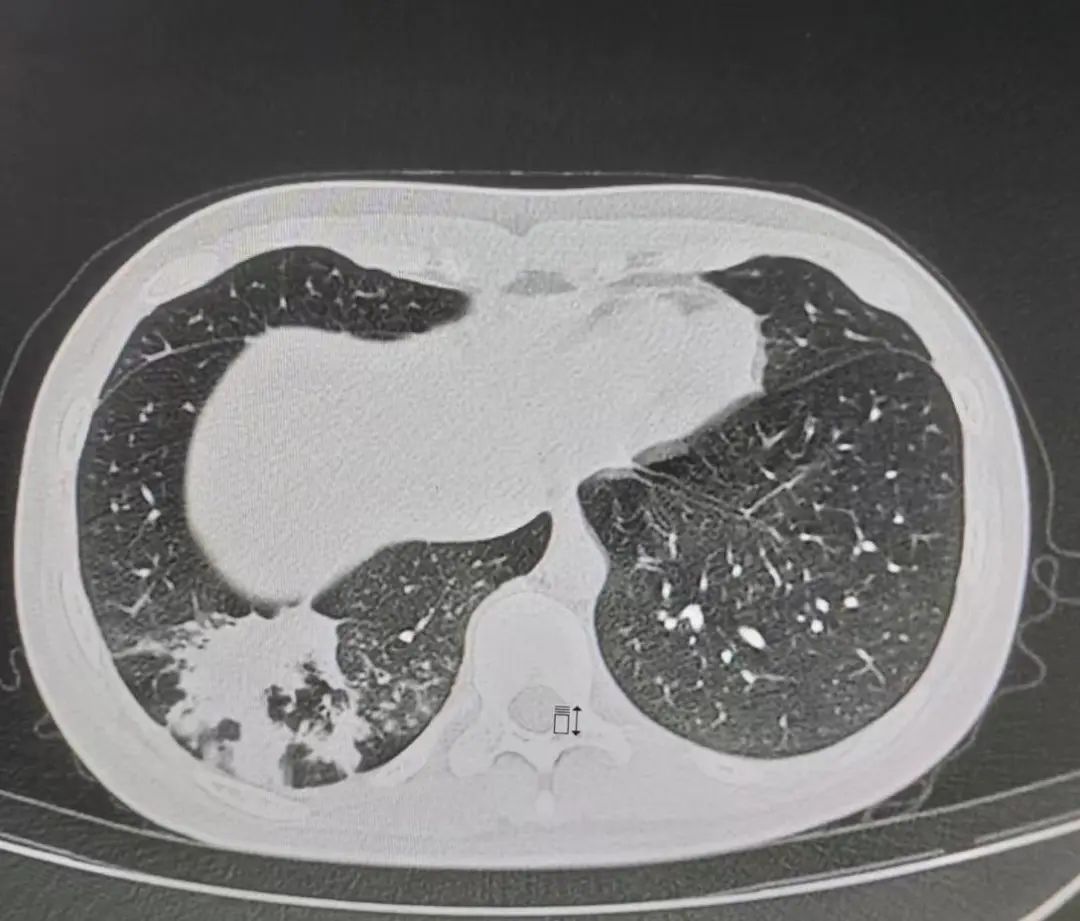

图1 入院治疗前胸部CT

患者是一名16岁的女性,既往体健,无高血压、冠心病、糖尿病史,无肝炎、结核等传染病史,无手术、外伤、输血史,无食物及药物过敏史,无吸烟、饮酒史。久居当地,未到过牧区及疫区。2022年5月底,患者接触感冒病人后出现发热,体温逐渐升至39.9℃,最高可达40.2℃,伴咳嗽、咳痰,为黄粘痰,自行口服头孢类抗菌药物后无改善。2022年6月2日,于他院就诊,进行相关化验检查,行胸部CT示右肺下叶炎症。进行呼吸道病原体检测,结果显示肺炎支原体阳性,确诊为支原体感染。给予复方甲氧那明、头孢唑肟钠、阿奇霉素、清开灵等药物治疗3天,患者仍间断高热,症状未见好转。后更换治疗药物为帕拉米韦、阿莫西林钠克拉维酸钾、赖氨西林、多西环素,患者症状仍未见好转。

后于6月7日行支气管镜检查,灌洗液NGS结果显示肺炎支原体,白色念珠菌为1*10^2/ml。6月9日,复查血常规,白细胞计数:2.24*10^9/L,淋巴细胞百分比:16.1%,中性粒细胞绝对值:1.59*10^9/L。复查胸部CT,对比6月2日,右肺下叶炎症较前范围增大,新增右侧胸腔少量积液,少量腹水。遂就诊于我院方舱,给予头孢曲松抗感染,排除新型冠状病毒感染可能性后,现为行进一步诊治收入我科(呼吸一科)。